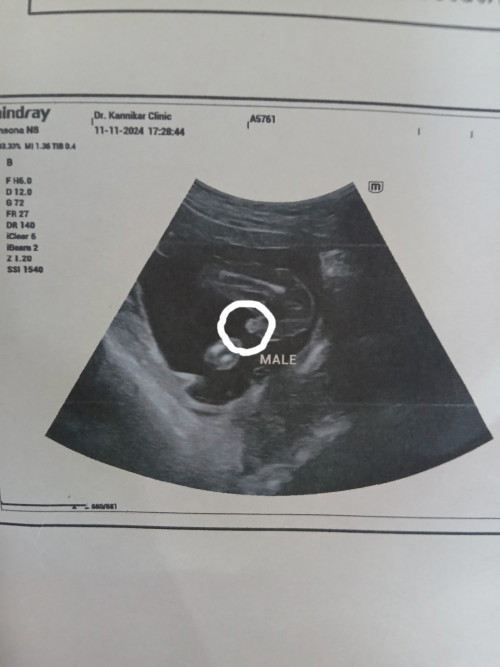

แม่ๆค่ะอายุครรภ์19สัปดา น้ำหนักน้อง284กรัม มากหรือน้อยไปค่ะ แบบนี้ ญ/ช ค่ะ

ตามมาตรฐาน240ค่ะ บ้านนี้ก้19วีค+2wหนัก331กรัมค่ะ /เพศขอเดาว่าผู้หญิงนะคะ เพราะว่าของเราไปซาวมาหมอบอกว่าถ้าเป็นผู้ชายจะมีจู๋ยื่นออกมาจากหว่างขาน้อง

ฟันธงยากค่ะ ว่านั้นไข่น้อง หรือน้องสาว รอซาวรอบหน้านะคะ แต่ส่วนตัวให้ลูกสาวค่ะ 😊

น่าจะหญิงค่ะแม่